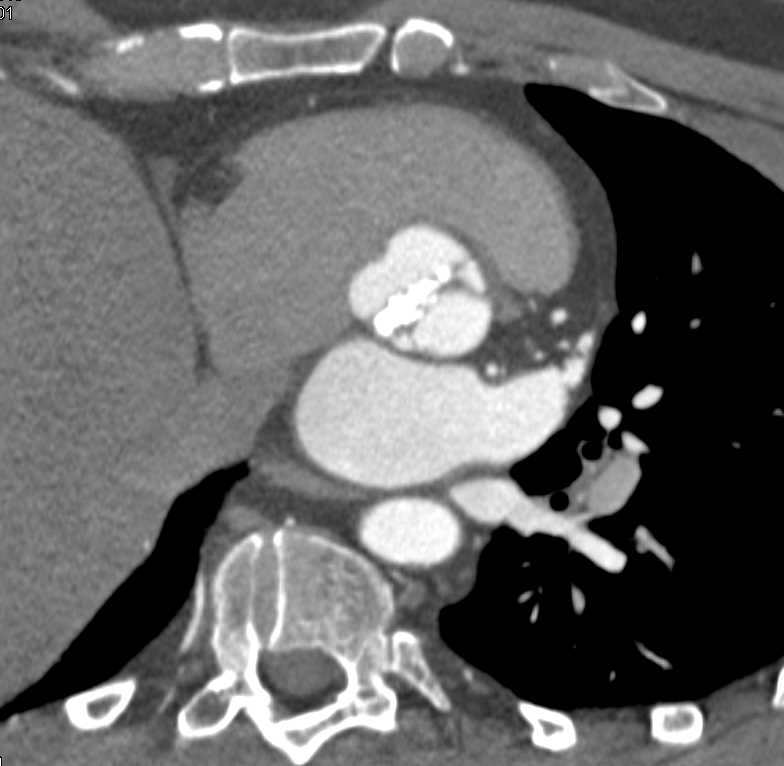

Tuberous Sclerosis with Lung Cysts and Incidental Renal Cell Carcinoma